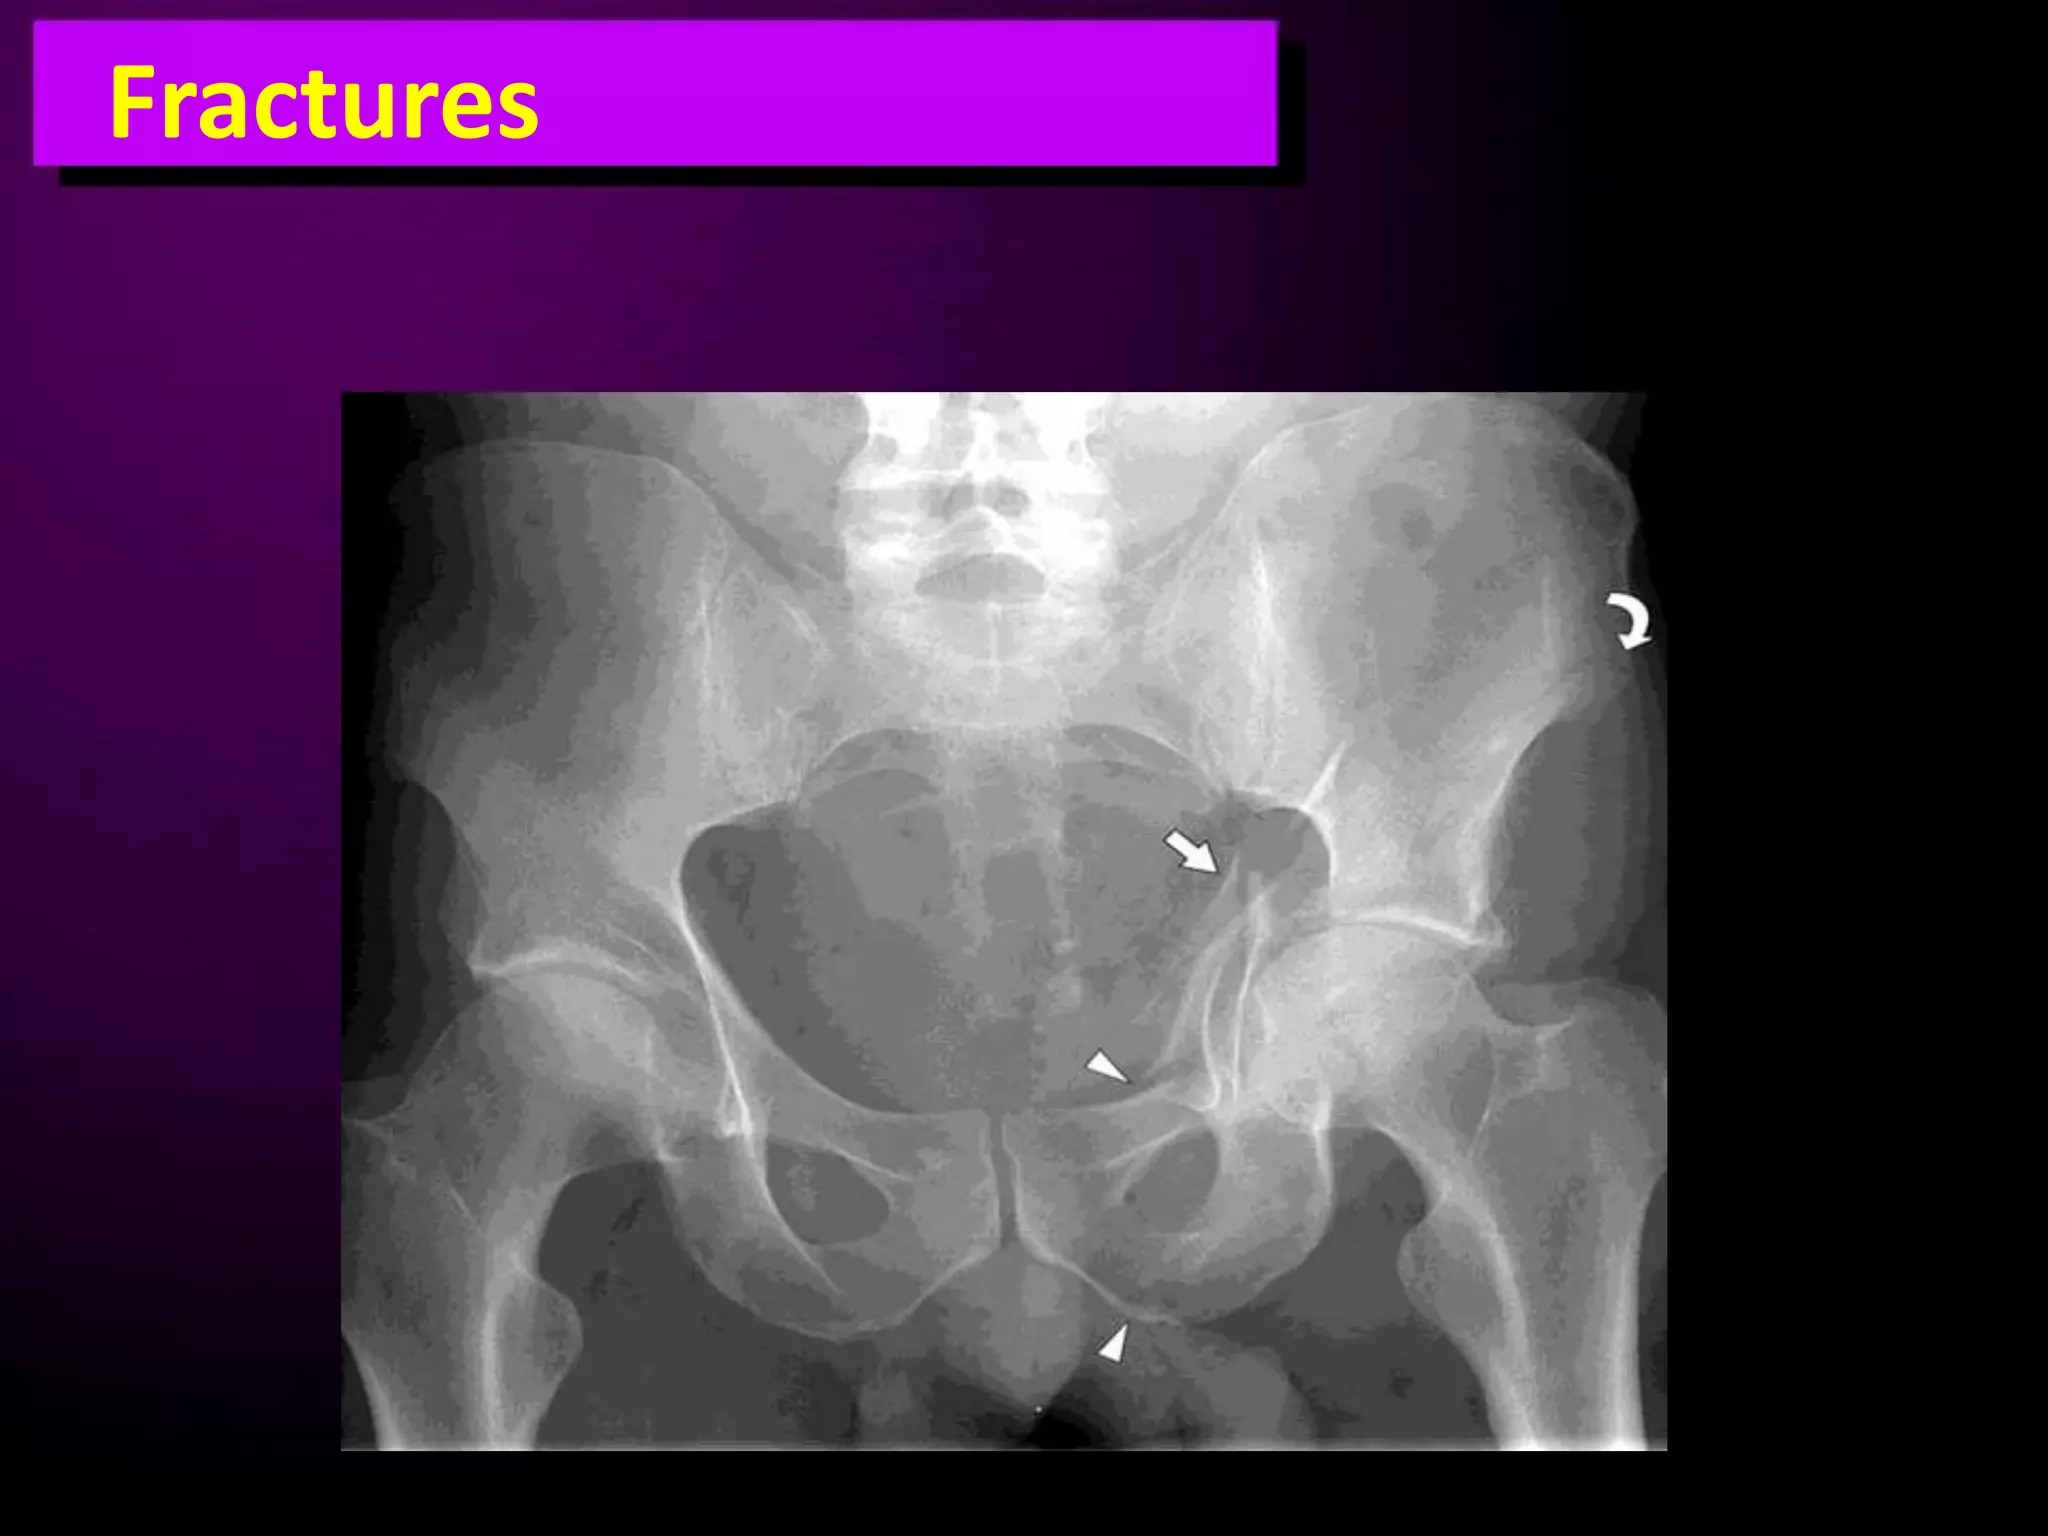

This document discusses trauma to the pelvis, hips, knees, ankles, and feet. It covers anatomy, imaging techniques, and types of fractures and dislocations that can occur in these areas. The types of fractures discussed include pelvic ring fractures, acetabular fractures, and fractures of the femur, tibia, fibula, and bones of the foot. Imaging views used include AP, inlet, and outlet views of the pelvis. Dislocations and fractures of the knee, ankle, and foot joints are also examined.